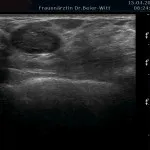

Mammasonographie:

Ultraschall_18